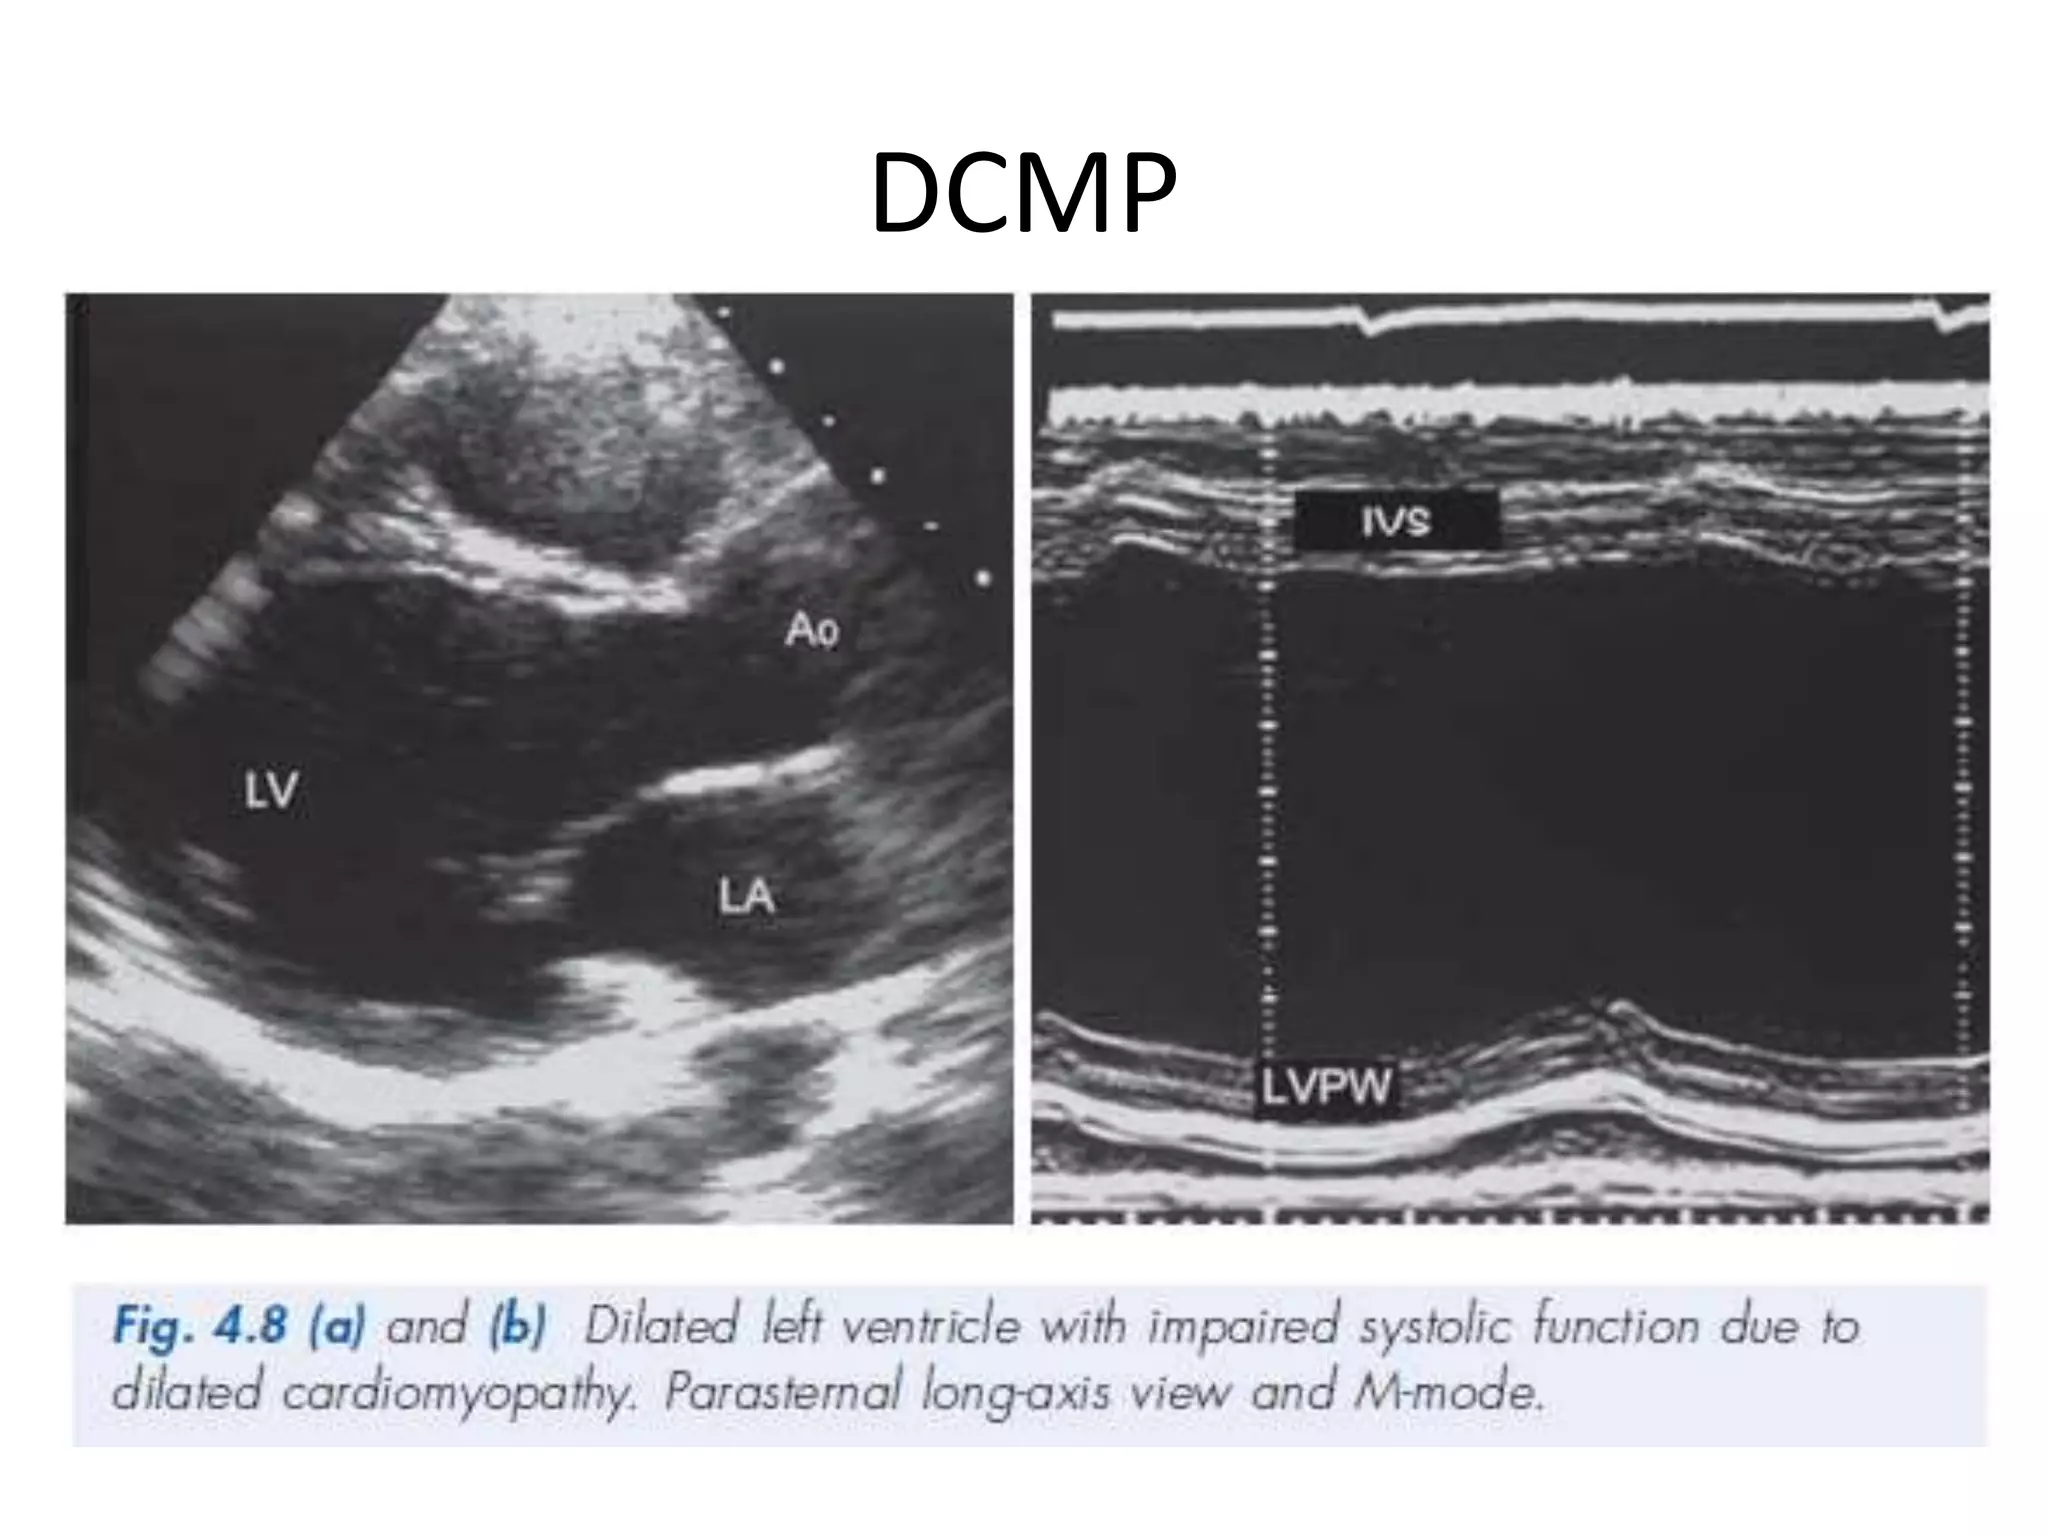

DCMP